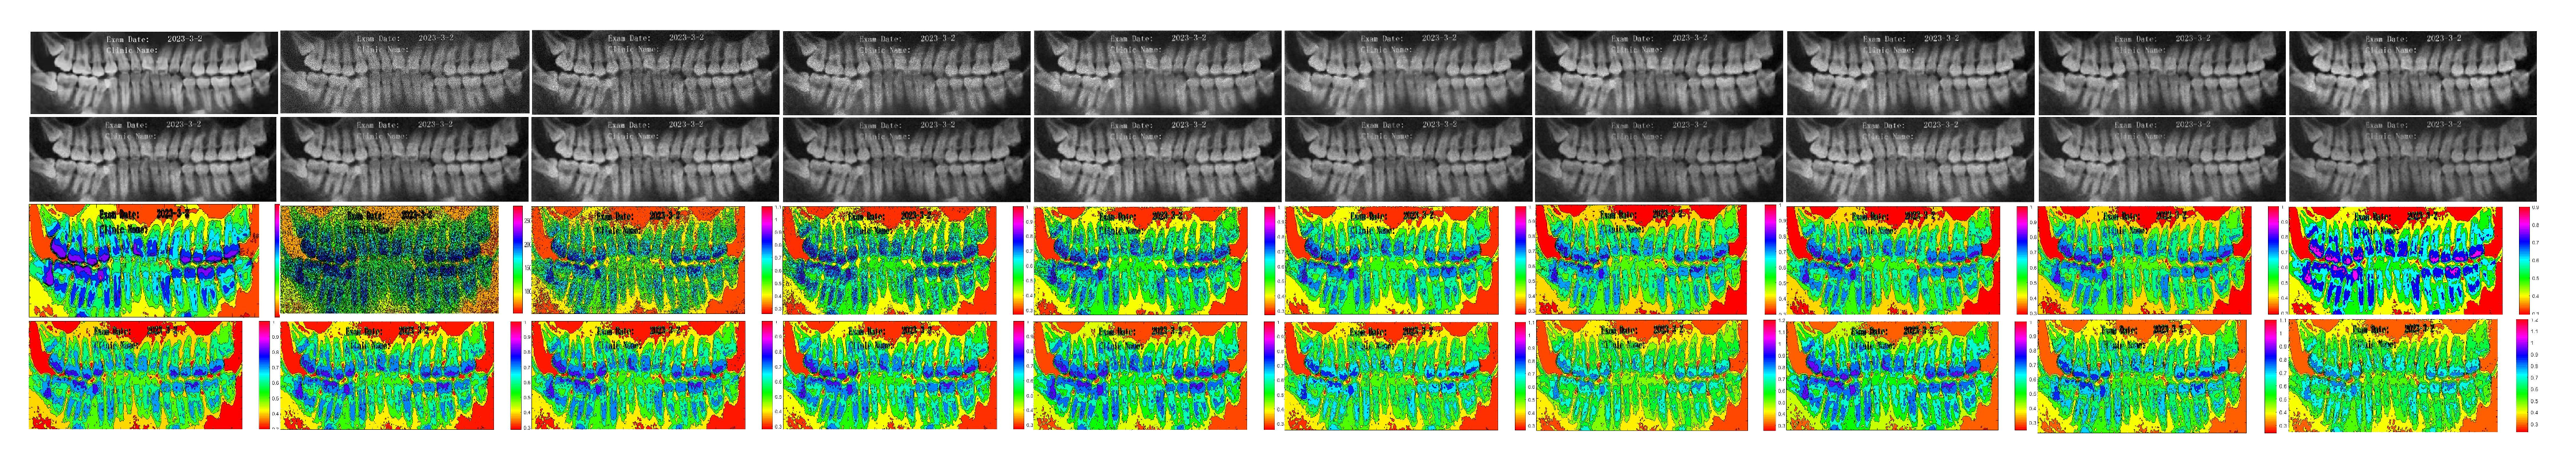

5.2. Numerical Simulations on Medical Images

5.2.2. Different Methods

- ADMM Method

5.2.3. Comparison with Other Variational Models